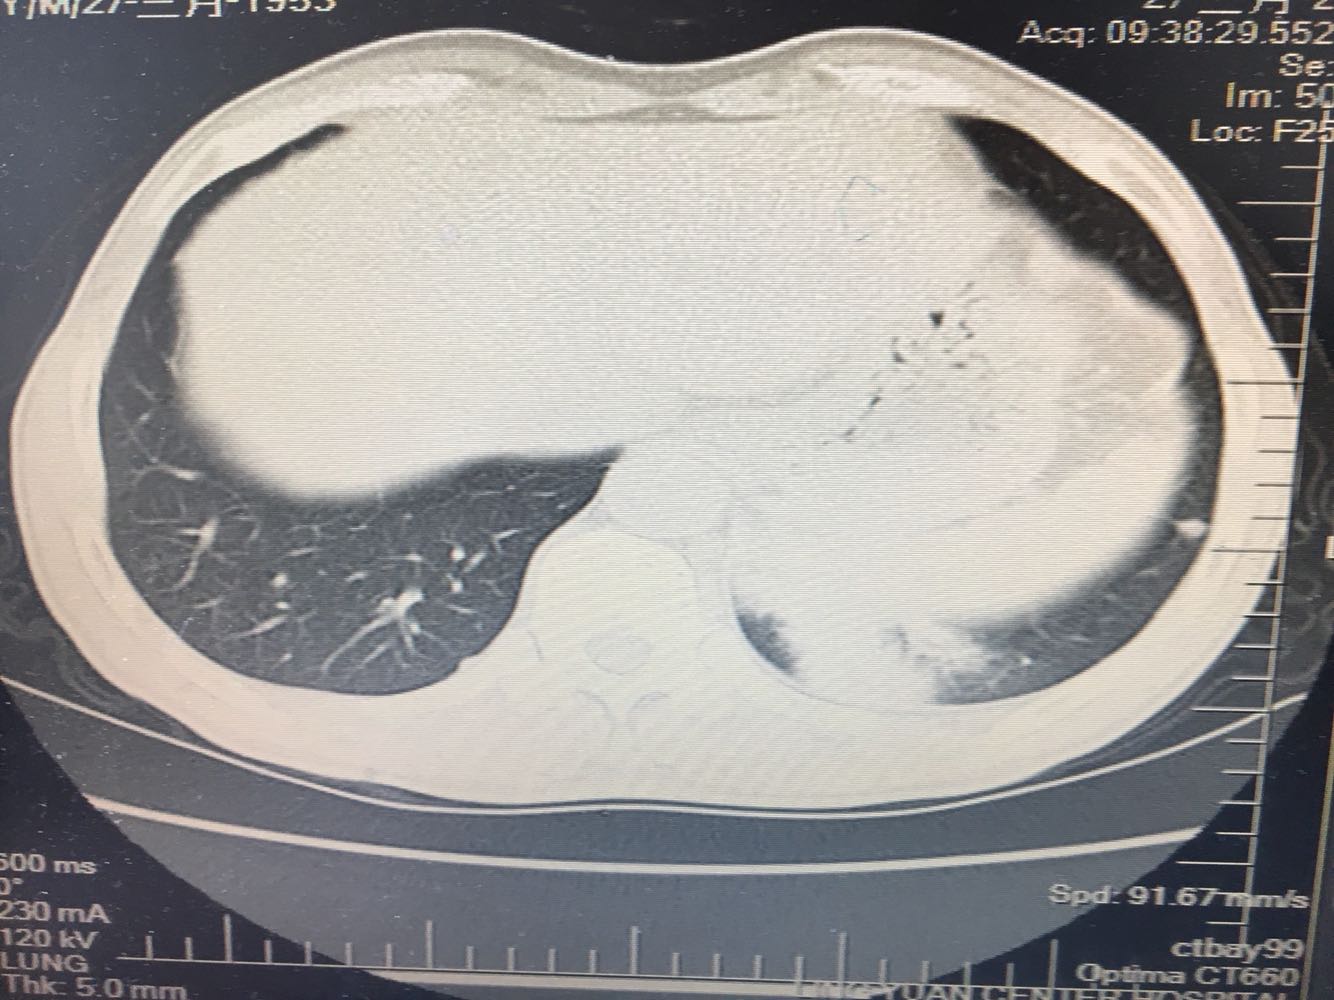

左肺下叶鳞癌

男,63岁,咳嗽1个月入院,患者自述1个月前无诱因咳嗽,阵发性干咳,无痰,时有血丝,无发热,左胸痛,活动后气短,静滴头孢13天无好转,门诊查肺CT后以 肺占位收入我科,病来饮食睡眠可,体重明显下降。既往疝气术后1年,吸烟史30年,每日1包。

左肺癌

左肺中央型肺癌,是否可以手术,还是化疗,放疗,靶向治疗?